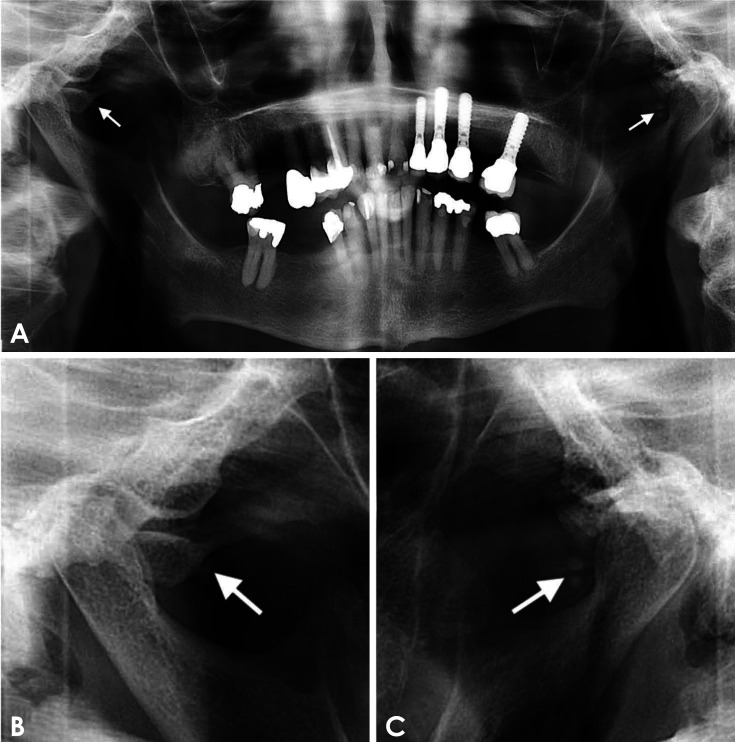

作者在本文中介绍了一例不寻常的病例,患者的咽鼓管钙化在全景图像上被伪装成颞下颌关节的松动放射斑,这给诊断带来了挑战。患者是一名 72 岁的女性,为改善咀嚼功能到牙科接受种植治疗。经口腔颌面放射医师委员会认证,该患者接受了锥形束计算机断层扫描。扫描结果显示,颞下颌关节没有钙化迹象;但双侧咽鼓管软骨部分发现结节状钙化。此外,本报告还简要回顾了颞下颌关节钙化松散体的鉴别诊断,并提供了需要定期加强的信息。

The author herein presents an unusual case of eustachian tube calcification masquerading as loose radiopacities in the temporomandibular joints on a panoramic image, creating a diagnostic challenge. The patient, a 72-year-old woman, presented to the dental service for implant treatment to improve her masticatory function. A cone-beam computed tomography scan was performed and reviewed by a board-certified oral and maxillofacial radiologist. The scan showed no evidence of calcifications in the temporomandibular joints; however, it revealed nodular calcifications within the cartilaginous portion of the eustachian tube bilaterally. Additionally, this report briefly reviews the differential diagnosis of calcified loose bodies in the temporomandibular joint and provides information that needs to be reinforced periodically.